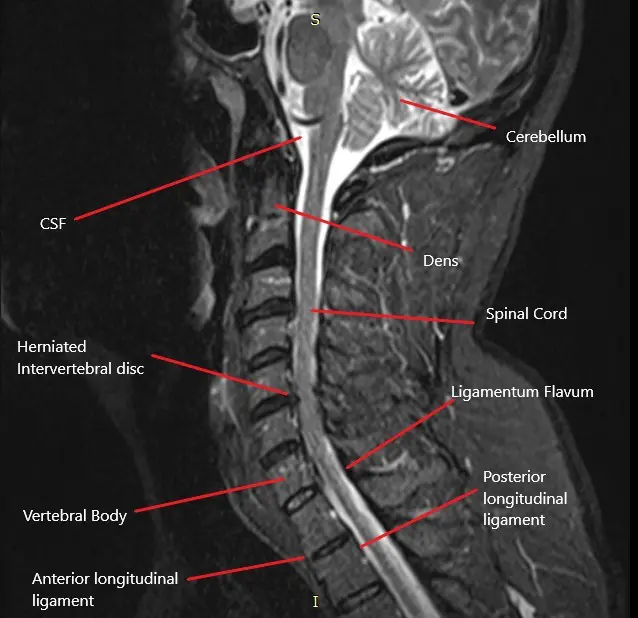

The cervical spine consists of seven vertebrae (C1-C7) in the neck region. Between each vertebra is an intervertebral disc that cushions and allows movement between the bones. The spinal cord passes through the central spinal canal, and nerves branch out from the spinal cord through the foramina (openings) in each vertebra. These nerves control sensation and movement in the shoulders, arms, hands, and other areas of the upper body. When a disc herniates, it can compress one or more of these nerves, leading to cervical radiculopathy.

- MRI: The gold standard imaging technique for identifying herniated discs, nerve compression, and other spinal abnormalities.

MRI helps visualize the herniated cervical disc and assess the extent of nerve root compression.